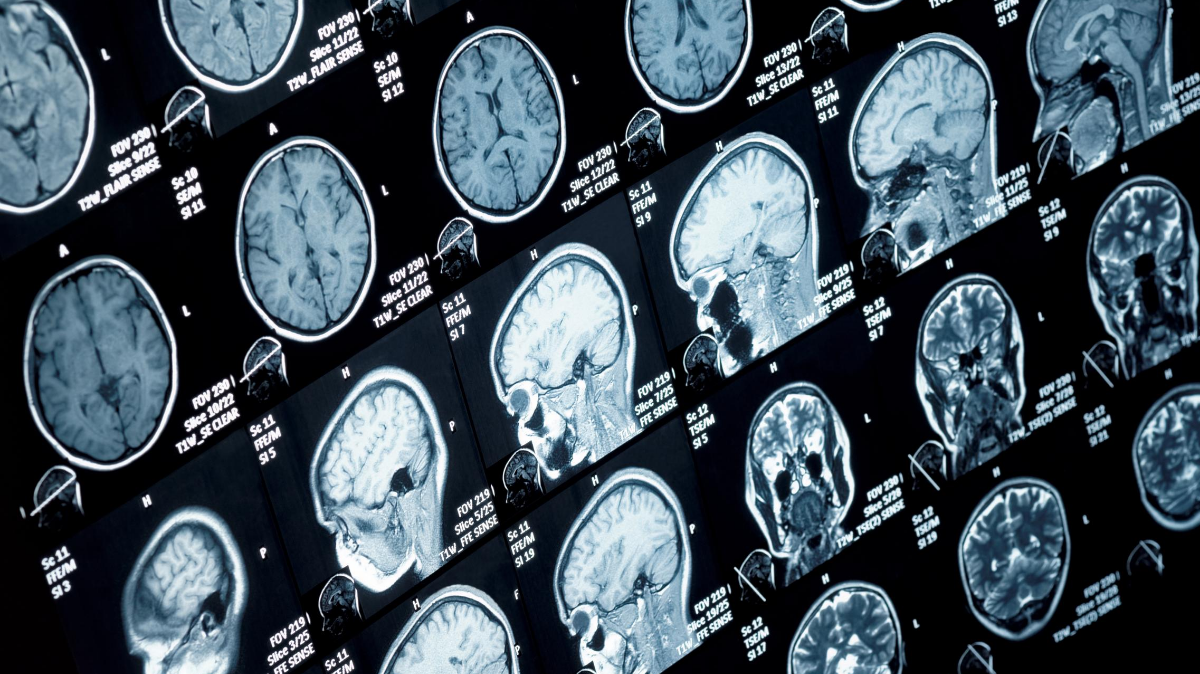

American Health Imaging is the largest provider of freestanding outpatient diagnostic imaging in the Southeast. We specialize in offering high quality MRIs, CTs, and Ultrasounds at a fraction of the cost of the high priced hospitals.